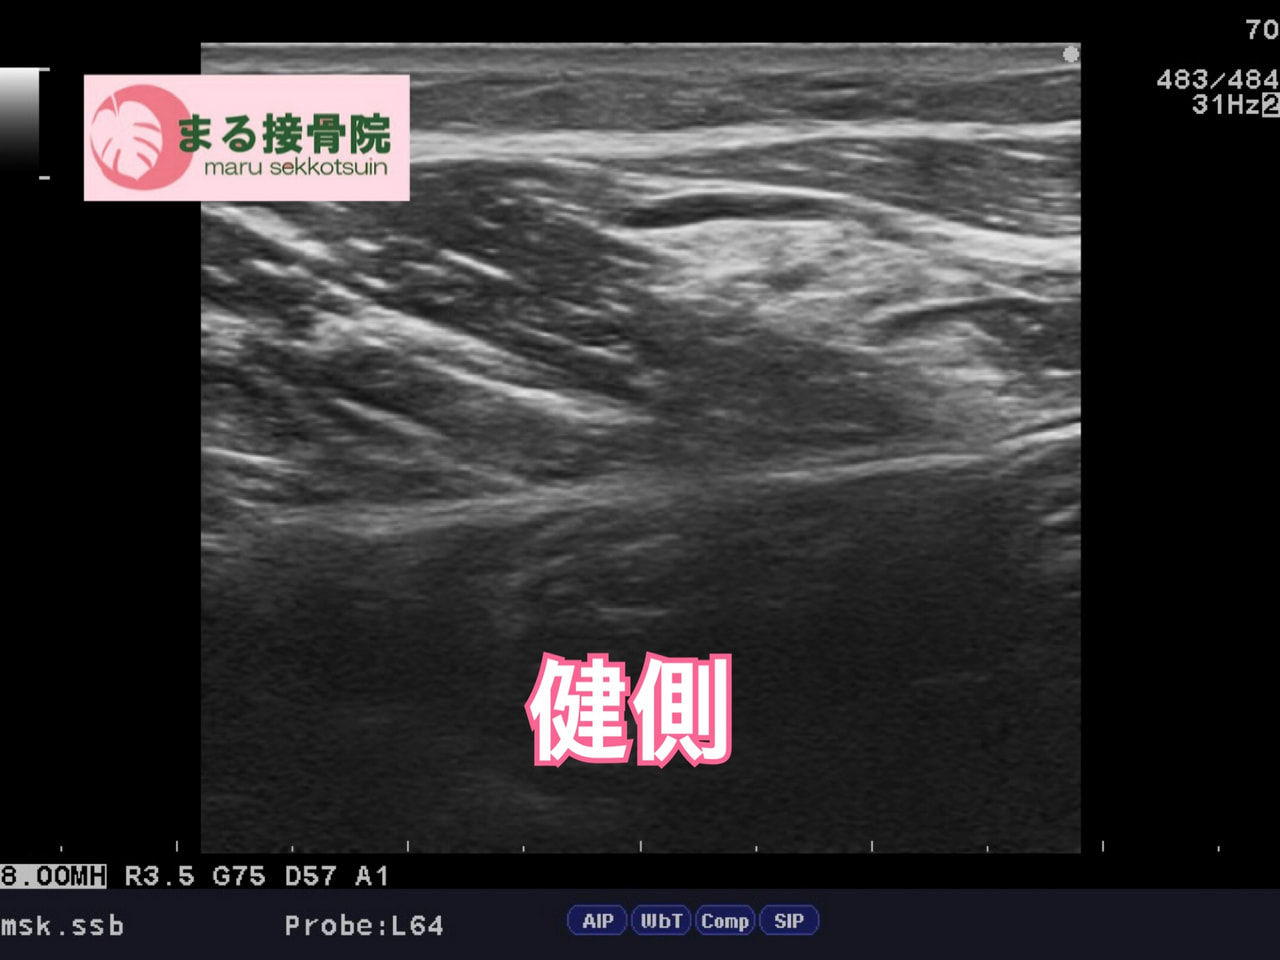

まる接骨院では、エコー検査を用いて損傷部位と程度を正確に確認し、

状態に合わせた施術を行います。